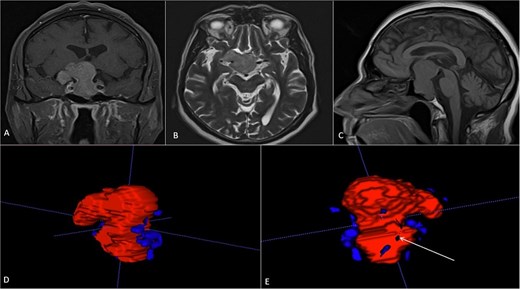

Case 3

A 68-year-old male patient with an 8-year history of gradual loss of visual acuity. An MRI study was performed with the following sequences: T1, T2, and T1 with contrast. When performing the three-dimensional segmentation, we realized the intimate relationship that the dorsum of the tumor had with the basilar artery; its dolichoectatic course on the dorsal surface of the tumor was what we paid the most attention to and what made us plan a better transnasal approach and avoid the traction of the capsule mainly the dorsal region (Fig. 6).

(A, B and C) MRI of pituitary marcoadenoma in coronal, axial and sagittal sections, contrasted T1, T2, and T1 sequences. (D and E) Planimetric segmentation with 3D reconstruction of the basilar and carotid system. White arrow, relationship of the dorsum of the tumor with the basilar artery.